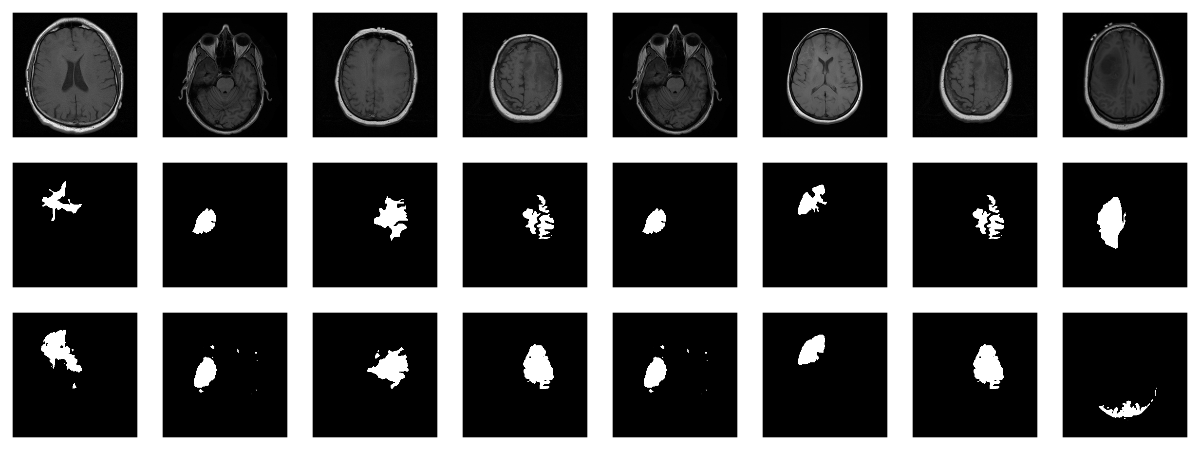

With U-Net, domain applicability is as broad as the architecture is flexible. Here, we want to detect abnormalities in brain scans. The dataset, used in Buda et al. (2019), contains MRI images together with manually created FLAIR abnormality segmentation masks. It is available on Kaggle .

As is often the case in medical imaging, there is notable class imbalance in the data. For every patient, sections have been taken at multiple positions. (Number of sections per patient varies.) Most sections do not exhibit any lesions; the corresponding masks are colored black everywhere.

Here are three examples where the masks do indicate abnormalities:

Let’s see if we can build a U-Net that generates such masks for us.